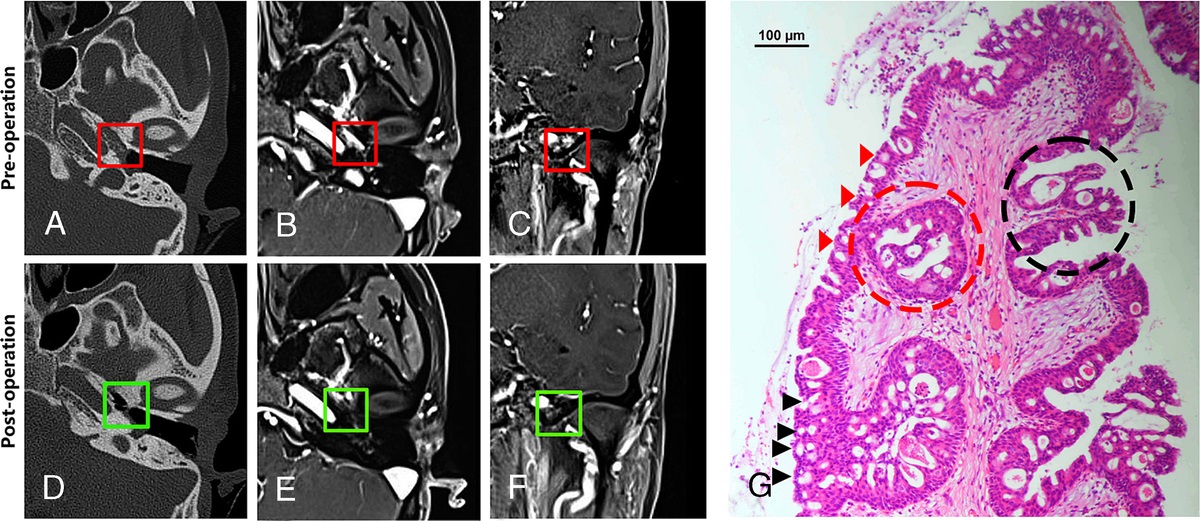

Key Genes and Endoscopic Radical Surgery in Primary Middle Ear Oncocytic Papillomas

Objective Papillomas originating from the Schneiderian epithelium within the middle ear are extre